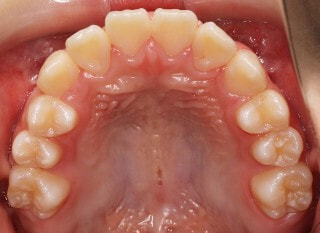

治療前

小児期第一段階

終了時